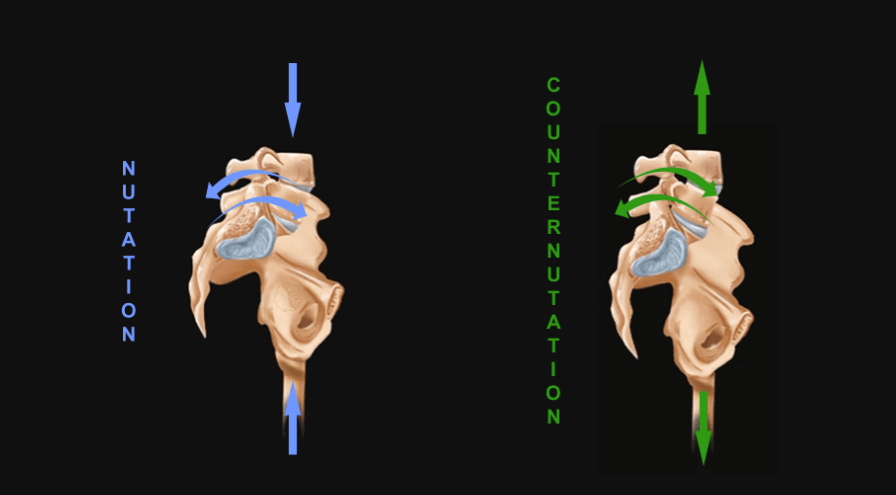

So, nutation is the motion that occurs when force (weight) is absorbed at our core, the sacroiliac joint, and occurs in the direction of gravitational forces (toward the ground). Counternutation is the body’s response, lifting the joint up against gravity.

At the sacroiliac joint, we consider the movement of the sacrum. Nutation occurs when the sacrum absorbs shock; it moves down, forward, and rotates to the opposite side. In rebound (counternutation) the sacrum moves up, backward, and rotates to the same side that absorbs the force.

At the same time, the ilium rotates in the opposite direction. Body weight causes the sacrum to move down and forward, while force from the ground, coming up through the legs, causes the ilium to move down and backward (for simplicity, we won’t discuss the rotational aspect). These two forces meet at the sacroiliac joint and force it into nutation. At the bottom point of nutation, the ligaments momentarily absorb the full weight, and the sacrum and ilium reverse direction, as they rebound into counternutation. However, when the force is greater than the ligaments can withstand, they sprain, and the core becomes unstable…more on that in another blog.